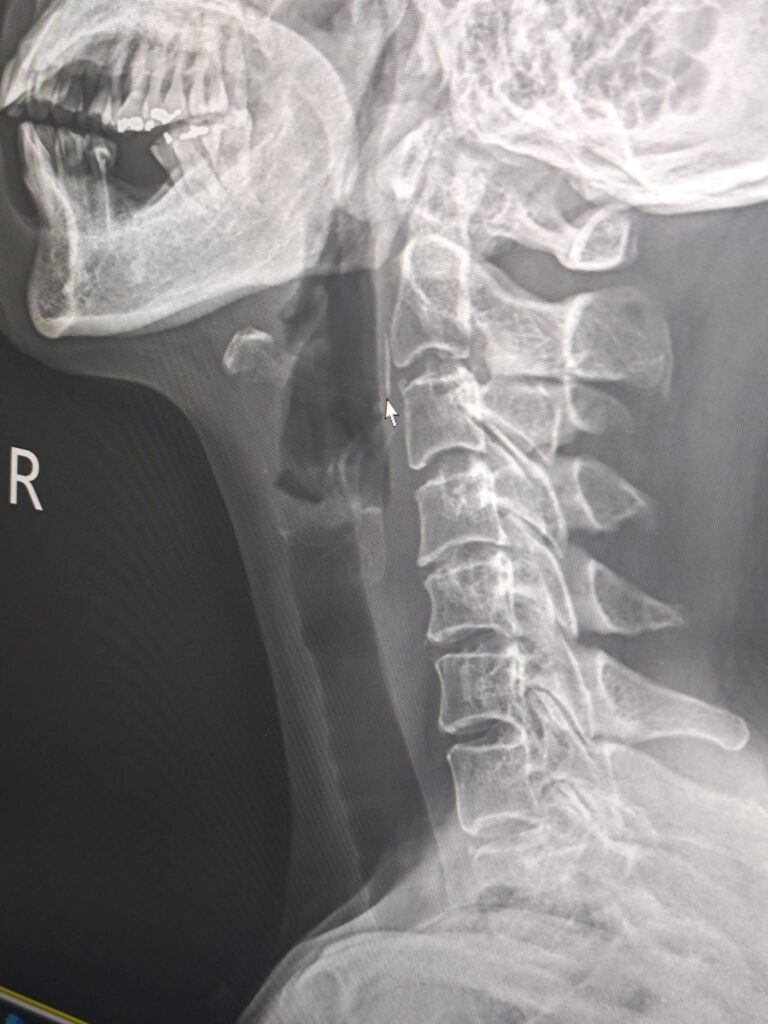

น่ากลัวมาก!! ก้างปลาติดคอ ทะลุออกมาหลังหู

หญิง แชร์อุทาหรณ์ ก้างปลาติดคอ จนมีอาการปวดข้างคอหลังใบหู สุดท้ายก้างทะลุออกมา

ตั้งแต่วันที่14เมษายน ที่ก้างปลาติดคอ 3 หมอบอกไม่น่ายังติดอยู่

ตัวเองก็คิดเช่นนั้น เพราะในคอไม่มีอาการเจ็บคอเวลาทานอาหาร แต่ยังสงสัยทำไมปวดตรงข้างคอด้านนอกหลังใบหู ก็พยายามเอามือจับกดดูทุกวัน และสงสัยว่าก้สงปลามันทิ่มออกมาด้านนอกได้มั๊ย

จนตอนดึกวันที่ 24 ตอนตี 2 ก็เกิดความสงสัยกดลงไปสัมผัสได้ถึงความแหลมของสิ่งที่อยู่ในคอ มั่นใจมากว่าต้องเป็นก้างปลา แต่ไม่กล้าดึง เพราะกลัวโดนเส้นเลือดหรือเส้นประสาท ตั้งไปหาหมอตอนเย็นวันเสาร

แต่ในวันที่ 25 เมษายน 2569 ตอนเช้า

ความประหลาดที่ไม่น่าเชื่อก้างปลาโผล่ออกมาสะดุดมือตอนล้างหน้าที่หลังหู เอามือจับดูแหลมเหมือนปลายเข็มโผล่ออกมานอกผิวหนัง จับค่อยๆดึงดูแน่ใจว่าเป็นก้างปลาแน่ ตัดสินใจดึงออก ผลคือเลือดพุ่งและก้างปลาติดมือมาเหมือนในฟิมล์เอ็กเรย์เลย

คุณพระช่วย,! ดีนะที่ออกมาข้างคอ ไม่พุ่งเข้าไปอยู่ในสมอง